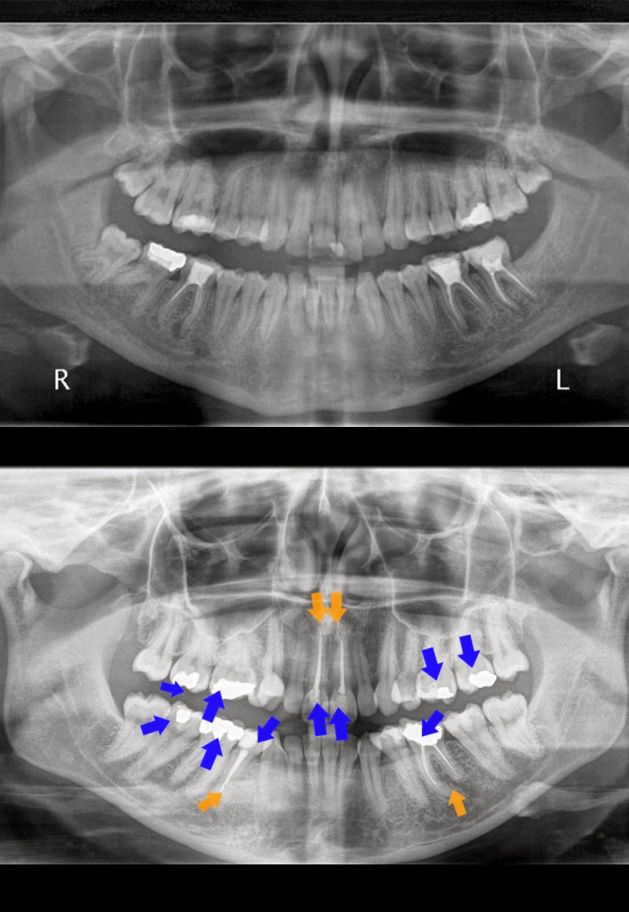

ΠΑΝΟΡΑΜΙΚΗ ΑΚΤΙΝΟΓΡΑΦΙΑ

Πολλές παθήσεις της στοματικής κοιλότητας, που αφορούν στα οστά της γνάθου, τα δόντια και τους περιβάλλοντες ιστούς δεν είναι ορατές, μετά από μια στοματολογική εξέταση. Η ψηφιακή πανοραμική ακτινογραφία σε συνδυασμό με την κλινική εξέταση, βοηθά:

• Στην διαπίστωση μικρών τερηδόνων μεταξύ των δοντιών ή τερηδόνων κάτω από υπάρχουσες αποκαταστάσεις, κατάγματων δοντιών, ακρορριζικών κύστεων, περιοδοντικής νόσου.

• Στον προεγχειρητικό έλεγχο γναθοπροσωπικών ανωμαλιών.

• Στην ανάδειξη αλλοιώσεων, οποιασδήποτε αιτιολογίας στα οστά των γνάθων.

• Στην ανάδειξη υπεράριθμων - εγκλείστων δοντιών.

• Στην μελέτη ορθοδοντικών προβλημάτων.

• Σε περιπτώσεις δυσλειτουργίας των κροταφογναθικών αρθρώσεων.

• Στην απεικόνιση ξένου σώματος στα οστά των γνάθων ή στα μαλακά μόρια της περιοχής του στόματος.

• Στον προεγχειρητικό και μετεγχειρητικό έλεγχο για την τοποθέτηση εμφυτευμάτων.

• Πριν απο την τοποθέτηση μερικών ή ολικών οδοντοστοιχιών καθώς και πρίν απο κάθε μορφής προσθετική εργασία.

• Στις περιπτώσεις καταγμάτων των οστών της γνάθου.